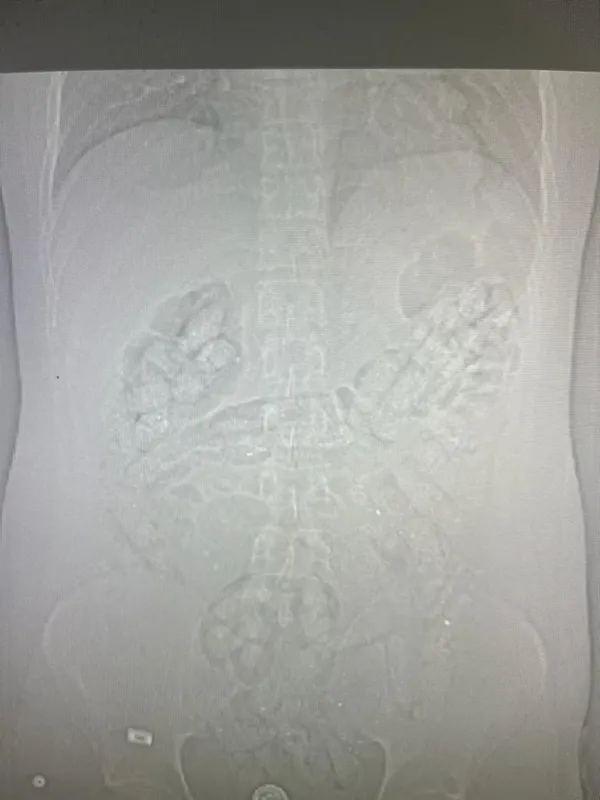

Erzincan İl Emniyet Müdürlüğü Narkotik Suçlarla Mücadele Şube Müdürlüğü ekiplerince uyuşturucu madde kuryeliği yapan şahıslara yönelik İran otobüsleri üzerinde yapılan uygulamada; İran otobüsünde yolculuk yapan Abdulmennan S. isimli İran uyruklu kişinin yutma yöntemiyle uyuşturucu taşıdığı değerlendirilmesi üzerine, Erzincan Mengücek Gazi Eğitim ve Araştırma Hastanesinde Abdulmennan S'nin bedeninden 106 fişek halinde toplamda 1 kilo 198 gram Afyon Sakızı ele geçirildi. Abdulmennan S. hakkında TCK 188 suçundan yapılan tahkikat sonrası sevk edildiği mahkemece tutuklanarak cezaevine teslim gönderildi.